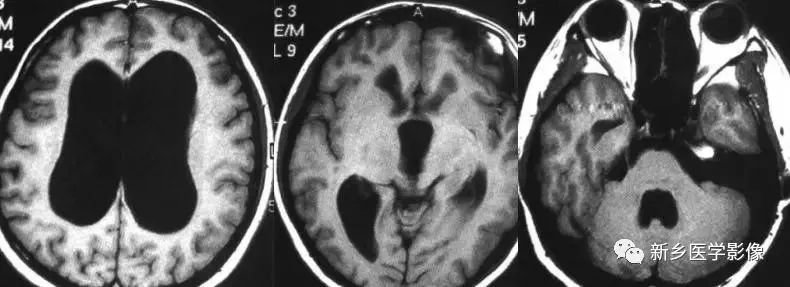

无脑回和巨脑回

无脑回和巨脑回是一组因神经元移行异常所致的脑回发育异常。巨脑回也称平滑脑。巨脑回指有部分脑回存在,这些脑回异常增大增宽、脑沟变浅。巨脑回主要位于额、颞部。无脑回主要位于顶、枕部。

临床上,无脑回和巨脑回畸形患儿均表现有小头畸形和轻微的面部异常,完全无脑回畸形常在两岁前死亡。不完全无脑回畸形通常能长期存活。

CT和MR均能够很好显示无脑回和巨脑回畸形,表现为大脑半球表面几乎呈光滑状,仅可见少数宽阔、粗大、平坦的脑回,脑沟缺如。脑灰质增厚、脑白质变薄,灰白质分界面异常平滑,见不到白质向灰质内伸入的现象。常见透明中隔腔存在,侧脑室扩大,蛛网膜下腔增宽。